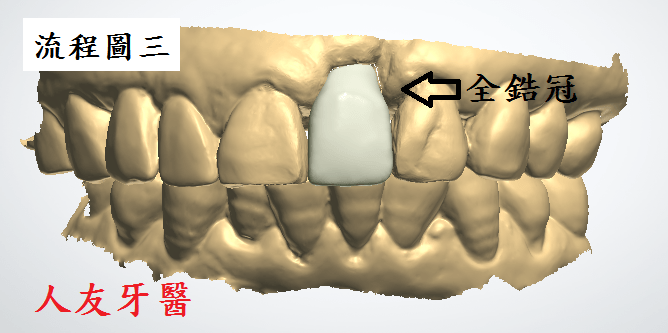

埋入植體後,待植牙骨密度到達標準值後再利用電腦掃描製作全鋯牙冠膺復

裝上全鋯牙冠(完成圖)

為何選擇全鋯牙冠

全鋯冠是由二氧化鋯製成,外層不燒上陶瓷,稱為全鋯牙冠,目前全鋯牙冠逐漸取代氧化鋯外層燒瓷的趨勢,也因為整顆是全鋯冠就不會發生瓷裂的問題,硬度絕佳,強度高於傳統的金屬假牙,此外傳統假牙密合度較差,不僅影響美觀上的視覺效果,更影響使用上的壽命

而現今已有3D口掃系統,在製作過程精準度遠高於傳統假牙印模方式,製作出的全鋯冠在密合度以及硬度和美觀上都遠比傳統金屬牙冠更進一步提升